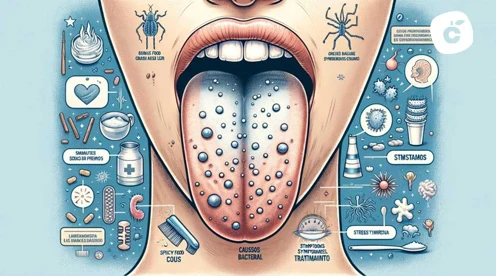

Descubre por qué salen granos en la lengua, si son peligrosos y cómo eliminarlos con tratamientos caseros o médicos. Cuándo preocuparse.

Las llagas en la punta de la lengua pueden deberse a aftas, irritaciones o deficiencias nutricionales. Descubre causas, tratamientos y cuándo acudir al dentista.